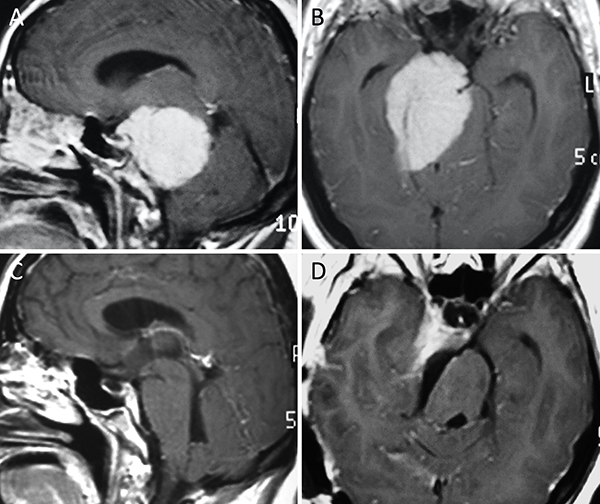

Figura 9. Meningioma del foramen magno anterior. A-B: RM preoperatoria; C-D: RM postoperatoria.